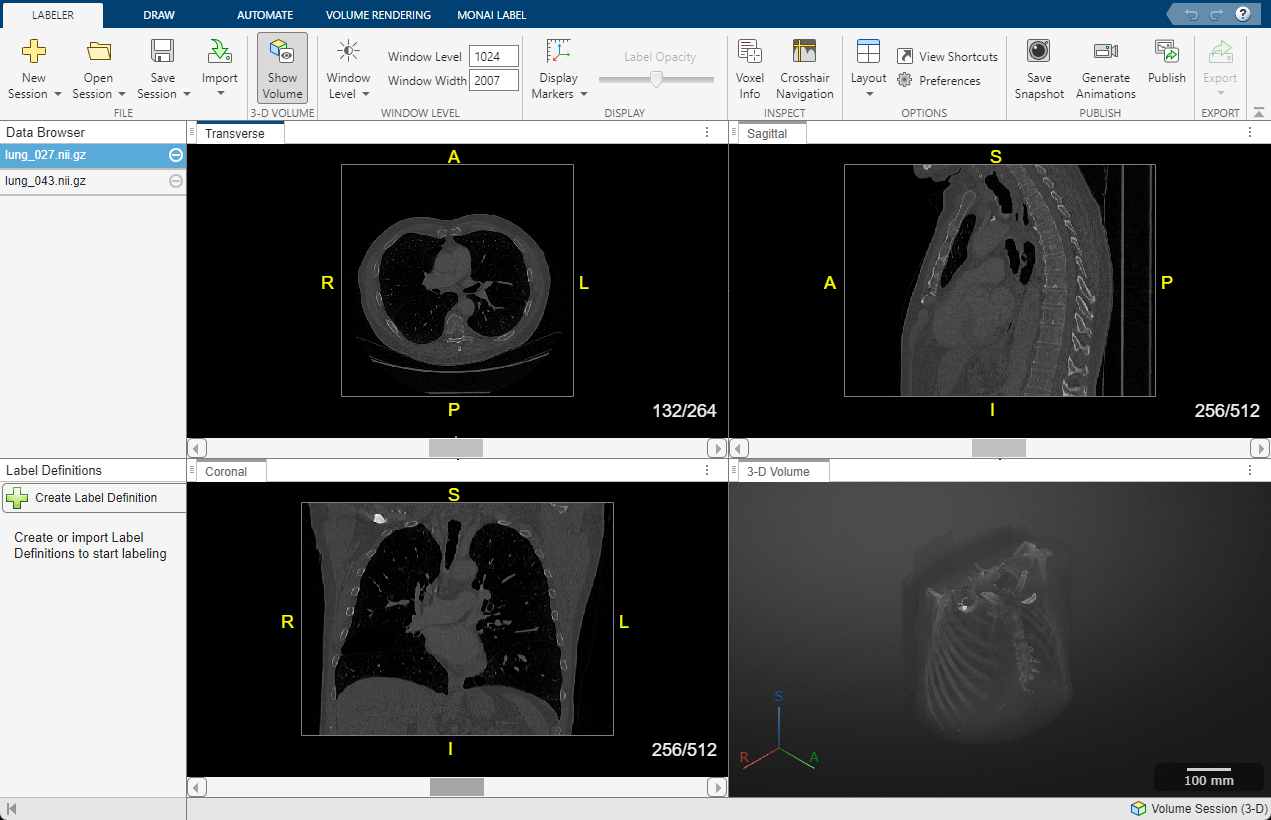

Screenshot mit transversalen, sagittalen, koronalen und 3D-Volumen-DICOM-Bilder einer Thorax-CT-Aufnahme mit Beschriftungen.

3D-Thorax-CT-Aufnahme im DICOM-Format visualisiert mithilfe des Medical Image Labeler in der Medical Imaging Toolbox. (Siehe Dokumentation.